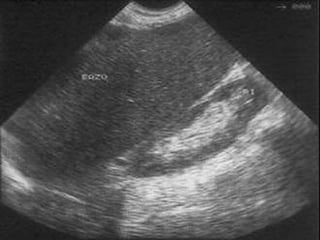

• #20 1º) Colocamos la sonda por debajo del apéndice xifoides (es el “pueblo de salida” o la “zona de aparcamiento”): -Es la zona de exploración del lóbulo hepático izquierdo. -Según dirijamos el haz de ultrasonidos hacia derecha o izquierda, irán apareciendo y desapareciendo distintas estructuras: *Si desde justo por debajo del apéndice xifoides, dirigimos el haz del ultrasonidos hacia la izquierda del paciente, iremos barriendo hasta su desaparición el lóbulo hepático izquierdo (a la vez que va desapareciendo el lóbulo hepático izquierdo, va apareciendo estómago). Cuando vemos el lóbulo hepático izquierdo, tenemos que valorar la homogeneidad del parénquima (es decir la textura), y los bordes hepáticos (son normales cuando son lineales, sin embargo si están nodulados quiere decir que es patológico). Nos tenemos que fijar además en el ángulo inferior hepático, que debe ser un ángulo agudo (acutángulo), ya que si aparece romo, indica malignidad. También veremos dentro del parénquima hepático dos tipos de vasos: vasos Portales (P-P: con Pared), y vasos Suprahepáticos (S-S: Sin pared). Los vasos suprahepáticos desembocaran en la cava inferior, que a su vez desembocará en aurícula derecha. *Una vez hemos barrido el lóbulo hepático izquierdo hacia nuestra derecha hasta su desaparición, volvemos barriendo ahora hacia nuestra izquierda hacia “zona de aparcamiento”, hasta que aparezca la arteria aorta y ahí estaremos en el “pueblo de la aorta” (tiene unas características propias: más ancha en craneal que en caudal; tiene un latido característico propio; es rectilínea). Hay que explorar toda la arteria aorta hasta su bifurcación en las arterias iliacas (posible asiento de aneurismas). ¿Qué tenemos que ver en el “pueblo de la aorta”?: Saliendo de la aorta, nos encontraremos que sale el tronco celiaco (más craneal) y la arteria mesentérica superior (más caudal).

• #21 1º) Colocamos la sonda por debajo del apéndice xifoides (es el “pueblo de salida” o la “zona de aparcamiento”): -Es la zona de exploración del lóbulo hepático izquierdo. -Según dirijamos el haz de ultrasonidos hacia derecha o izquierda, irán apareciendo y desapareciendo distintas estructuras: *Si desde justo por debajo del apéndice xifoides, dirigimos el haz del ultrasonidos hacia la izquierda del paciente, iremos barriendo hasta su desaparición el lóbulo hepático izquierdo (a la vez que va desapareciendo el lóbulo hepático izquierdo, va apareciendo estómago). Cuando vemos el lóbulo hepático izquierdo, tenemos que valorar la homogeneidad del parénquima (es decir la textura), y los bordes hepáticos (son normales cuando son lineales, sin embargo si están nodulados quiere decir que es patológico). Nos tenemos que fijar además en el ángulo inferior hepático, que debe ser un ángulo agudo (acutángulo), ya que si aparece romo, indica malignidad. También veremos dentro del parénquima hepático dos tipos de vasos: vasos Portales (P-P: con Pared), y vasos Suprahepáticos (S-S: Sin pared). Los vasos suprahepáticos desembocaran en la cava inferior, que a su vez desembocará en aurícula derecha. *Una vez hemos barrido el lóbulo hepático izquierdo hacia nuestra derecha hasta su desaparición, volvemos barriendo ahora hacia nuestra izquierda hacia “zona de aparcamiento”, hasta que aparezca la arteria aorta y ahí estaremos en el “pueblo de la aorta” (tiene unas características propias: más ancha en craneal que en caudal; tiene un latido característico propio; es rectilínea). Hay que explorar toda la arteria aorta hasta su bifurcación en las arterias iliacas (posible asiento de aneurismas). ¿Qué tenemos que ver en el “pueblo de la aorta”?: Saliendo de la aorta, nos encontraremos que sale el tronco celiaco (más craneal) y la arteria mesentérica superior (más caudal).

• #22 1º) Colocamos la sonda por debajo del apéndice xifoides (es el “pueblo de salida” o la “zona de aparcamiento”): -Es la zona de exploración del lóbulo hepático izquierdo. -Según dirijamos el haz de ultrasonidos hacia derecha o izquierda, irán apareciendo y desapareciendo distintas estructuras: *Si desde justo por debajo del apéndice xifoides, dirigimos el haz del ultrasonidos hacia la izquierda del paciente, iremos barriendo hasta su desaparición el lóbulo hepático izquierdo (a la vez que va desapareciendo el lóbulo hepático izquierdo, va apareciendo estómago). Cuando vemos el lóbulo hepático izquierdo, tenemos que valorar la homogeneidad del parénquima (es decir la textura), y los bordes hepáticos (son normales cuando son lineales, sin embargo si están nodulados quiere decir que es patológico). Nos tenemos que fijar además en el ángulo inferior hepático, que debe ser un ángulo agudo (acutángulo), ya que si aparece romo, indica malignidad. También veremos dentro del parénquima hepático dos tipos de vasos: vasos Portales (P-P: con Pared), y vasos Suprahepáticos (S-S: Sin pared). Los vasos suprahepáticos desembocaran en la cava inferior, que a su vez desembocará en aurícula derecha. *Una vez hemos barrido el lóbulo hepático izquierdo hacia nuestra derecha hasta su desaparición, volvemos barriendo ahora hacia nuestra izquierda hacia “zona de aparcamiento”, hasta que aparezca la arteria aorta y ahí estaremos en el “pueblo de la aorta” (tiene unas características propias: más ancha en craneal que en caudal; tiene un latido característico propio; es rectilínea). Hay que explorar toda la arteria aorta hasta su bifurcación en las arterias iliacas (posible asiento de aneurismas). ¿Qué tenemos que ver en el “pueblo de la aorta”?: Saliendo de la aorta, nos encontraremos que sale el tronco celiaco (más craneal) y la arteria mesentérica superior (más caudal).

• #25 1º) Colocamos la sonda por debajo del apéndice xifoides (es el “pueblo de salida” o la “zona de aparcamiento”): -Es la zona de exploración del lóbulo hepático izquierdo. -Según dirijamos el haz de ultrasonidos hacia derecha o izquierda, irán apareciendo y desapareciendo distintas estructuras: *Si desde justo por debajo del apéndice xifoides, dirigimos el haz del ultrasonidos hacia la izquierda del paciente, iremos barriendo hasta su desaparición el lóbulo hepático izquierdo (a la vez que va desapareciendo el lóbulo hepático izquierdo, va apareciendo estómago). Cuando vemos el lóbulo hepático izquierdo, tenemos que valorar la homogeneidad del parénquima (es decir la textura), y los bordes hepáticos (son normales cuando son lineales, sin embargo si están nodulados quiere decir que es patológico). Nos tenemos que fijar además en el ángulo inferior hepático, que debe ser un ángulo agudo (acutángulo), ya que si aparece romo, indica malignidad. También veremos dentro del parénquima hepático dos tipos de vasos: vasos Portales (P-P: con Pared), y vasos Suprahepáticos (S-S: Sin pared). Los vasos suprahepáticos desembocaran en la cava inferior, que a su vez desembocará en aurícula derecha. *Una vez hemos barrido el lóbulo hepático izquierdo hacia nuestra derecha hasta su desaparición, volvemos barriendo ahora hacia nuestra izquierda hacia “zona de aparcamiento”, hasta que aparezca la arteria aorta y ahí estaremos en el “pueblo de la aorta” (tiene unas características propias: más ancha en craneal que en caudal; tiene un latido característico propio; es rectilínea). Hay que explorar toda la arteria aorta hasta su bifurcación en las arterias iliacas (posible asiento de aneurismas). ¿Qué tenemos que ver en el “pueblo de la aorta”?: Saliendo de la aorta, nos encontraremos que sale el tronco celiaco (más craneal) y la arteria mesentérica superior (más caudal).

• #26 1º) Colocamos la sonda por debajo del apéndice xifoides (es el “pueblo de salida” o la “zona de aparcamiento”): -Es la zona de exploración del lóbulo hepático izquierdo. -Según dirijamos el haz de ultrasonidos hacia derecha o izquierda, irán apareciendo y desapareciendo distintas estructuras: *Si desde justo por debajo del apéndice xifoides, dirigimos el haz del ultrasonidos hacia la izquierda del paciente, iremos barriendo hasta su desaparición el lóbulo hepático izquierdo (a la vez que va desapareciendo el lóbulo hepático izquierdo, va apareciendo estómago). Cuando vemos el lóbulo hepático izquierdo, tenemos que valorar la homogeneidad del parénquima (es decir la textura), y los bordes hepáticos (son normales cuando son lineales, sin embargo si están nodulados quiere decir que es patológico). Nos tenemos que fijar además en el ángulo inferior hepático, que debe ser un ángulo agudo (acutángulo), ya que si aparece romo, indica malignidad. También veremos dentro del parénquima hepático dos tipos de vasos: vasos Portales (P-P: con Pared), y vasos Suprahepáticos (S-S: Sin pared). Los vasos suprahepáticos desembocaran en la cava inferior, que a su vez desembocará en aurícula derecha. *Una vez hemos barrido el lóbulo hepático izquierdo hacia nuestra derecha hasta su desaparición, volvemos barriendo ahora hacia nuestra izquierda hacia “zona de aparcamiento”, hasta que aparezca la arteria aorta y ahí estaremos en el “pueblo de la aorta” (tiene unas características propias: más ancha en craneal que en caudal; tiene un latido característico propio; es rectilínea). Hay que explorar toda la arteria aorta hasta su bifurcación en las arterias iliacas (posible asiento de aneurismas). ¿Qué tenemos que ver en el “pueblo de la aorta”?: Saliendo de la aorta, nos encontraremos que sale el tronco celiaco (más craneal) y la arteria mesentérica superior (más caudal).